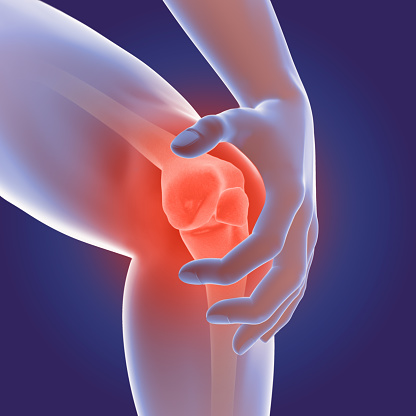

3D printing could provide treatment to osteoarthritis patients in the near future